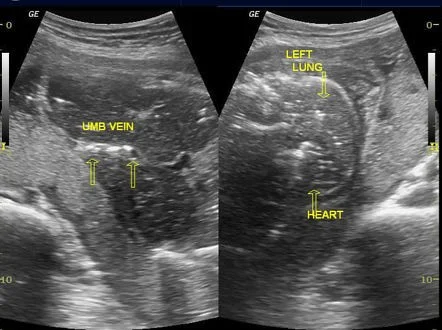

- Ultrasonography ( accurate 100% )

- Spalding sign (irregular overlapping of skull bones after 7days) - 1st img

- Robert’s sign (gas shadows in the chambers of the heart & great vessels after 12h) - 2nd img